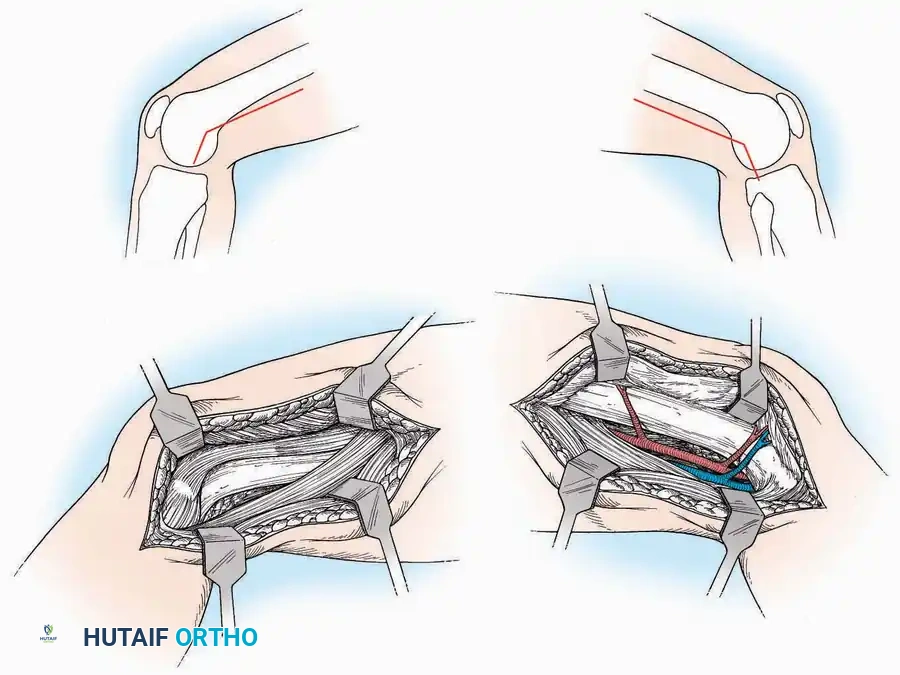

Approaches to the Interphalangeal (IP) Joints

Indications: Arthrodesis for hammer toe deformities, excision of intra-articular osteophytes, or reduction of irreducible dislocations.

Surgical Technique:

* Great Toe: Make a 2.5 cm longitudinal incision strictly on the medial midaxial aspect of the toe.

* Fifth Toe: Utilize a lateral midaxial incision to avoid interdigital maceration.

* Lesser Toes (2nd, 3rd, 4th): Approach the IP joints through a dorsal longitudinal incision placed just lateral to the corresponding extensor digitorum longus (EDL) tendon.

* Deep Dissection: Carry the dissection sharply through the subcutaneous tissue and superficial fascia directly to the joint capsule.

* Neurovascular Protection: Reflect the skin edges with meticulous care. Retract the dorsal digital nerves and vessels dorsally, and the plantar nerves and vessels plantarward.

* Capsulotomy: Open the capsule either transversely (for joint resection/arthrodesis) or longitudinally (for exploration), exposing the articular surfaces.